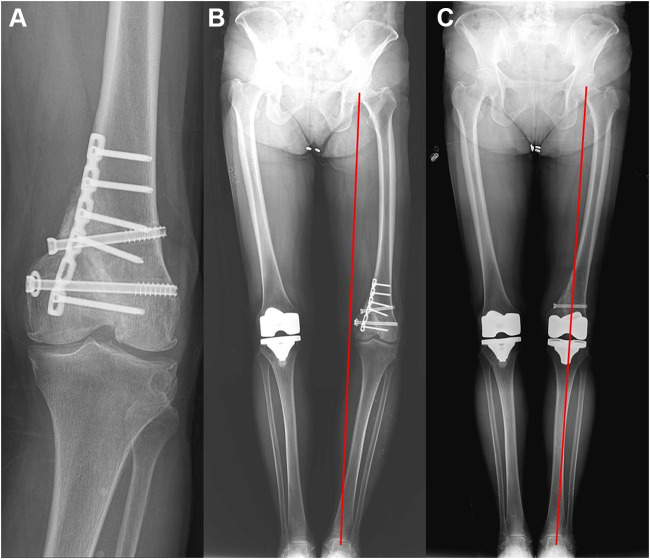

背景:在股骨或胫骨创伤后关节外畸形的情况下,实现适当的轴对齐可能是困难的。我们介绍了机器人辅助全膝关节置换术(TKA)对伴有创伤后关节外畸形的膝关节骨性关节炎患者的放射学结果。方法:我们分析了5例患者(1)Kellgren-Lawrence (K-L) III-IV级骨关节炎膝关节,(2)股骨或胫骨存在创伤后关节外畸形,(3)接受机器人辅助TKA的患者的5个膝关节的结局。对他们的放射学表现进行了评估。结果:所有初始畸形的5个膝关节(平均14.8°,范围12.7-18.5°)均被矫正为中立位(平均0.7°,范围-1.1-2.7°)。术后髋关节-膝关节-踝关节(HKA)角度无异常值。结论:我们的研究结果表明,机器人辅助的TKA可以用于创伤后关节外畸形患者实现正确的肢体对准。

Methods: We analyzed the outcomes of five knees in five patients with (1) Kellgren-Lawrence (K-L) Grade III-IV osteoarthritic knees, (2) the presence of posttraumatic extra-articular deformities either in the femur or the tibia, and (3) who underwent robot-assisted TKA. Their radiological findings were evaluated.

Results: All five knees with initial deformity (mean 14.8°, range 12.7-18.5°) were corrected to neutral alignment (mean 0.7°, range -1.1-2.7°). There was no postoperative outlier of hip-knee-ankle (HKA) angle.